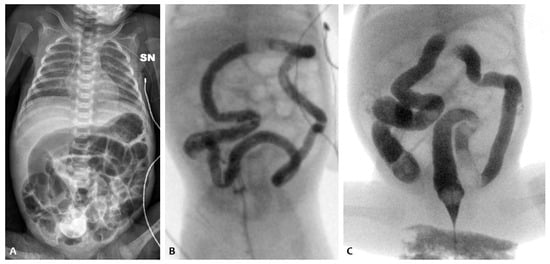

She was then transferred to our NICU to undergo percutaneous closure of the PDA performed at around 34 days of life, in the absence of postoperative complications. Despite the closure of the PDA, the subsequent attempt at enteral feeding was followed by abdominal distension initially attributed to reperfusion syndrome. Abdominal ultrasonography revealed no signs of pneumatosis and no intestinal and biliary tract abnormalities. Serial abdomen X-ray exams showed diffuse intestinal dilatation and no evidence of intra-abdominal free air (Figure 2A). Relevant abdominal distention persisted, and during this period, there was no spontaneous stool production. A contrast enema was performed using the nonionic dimer contrast agent iodixanol 320 (Visipaque) and showed dolichosigma exclusively. Barium enema and small bowel enema studies were performed, with normal results. Newborn metabolic screening and genetic tests for cystic fibrosis were negative. We found no hormone anomalies.

At around 56 days of life, in the suspicion of an intestinal motility disorder, therapy was started by nasogastric tube with amoxicillin–clavulanic acid at a dosage of 10 mg/kg twice a day, and at the same time, NAC rectal enemas were started twice a day. The execution of the enemas determined the emission of stools (normal color and consistency) but without improvement in abdominal distension.

On the 86th day of life (Figure 2B), postponed due to an episode of sepsis caused by Serratia marcescens, minimal enteral feeding (using breast milk) was started in association with the administration of NAC via a nasogastric tube. With the introduction of NAC treatment, there was a regularization of the frequency and consistency of the stools andan absence of clinically relevant abdominal distension (Figure 2C), which made it possible to reach full enteral feeding and weight gain. The infant was discharged home with full oral feeding on day 110.

Figure 2. Abdominal X-ray of patient P2 on the 36th day of life (A); persistent abdominal distension on the 86th day of life (B); and abdominal X-ray after the NAC treatment (C).